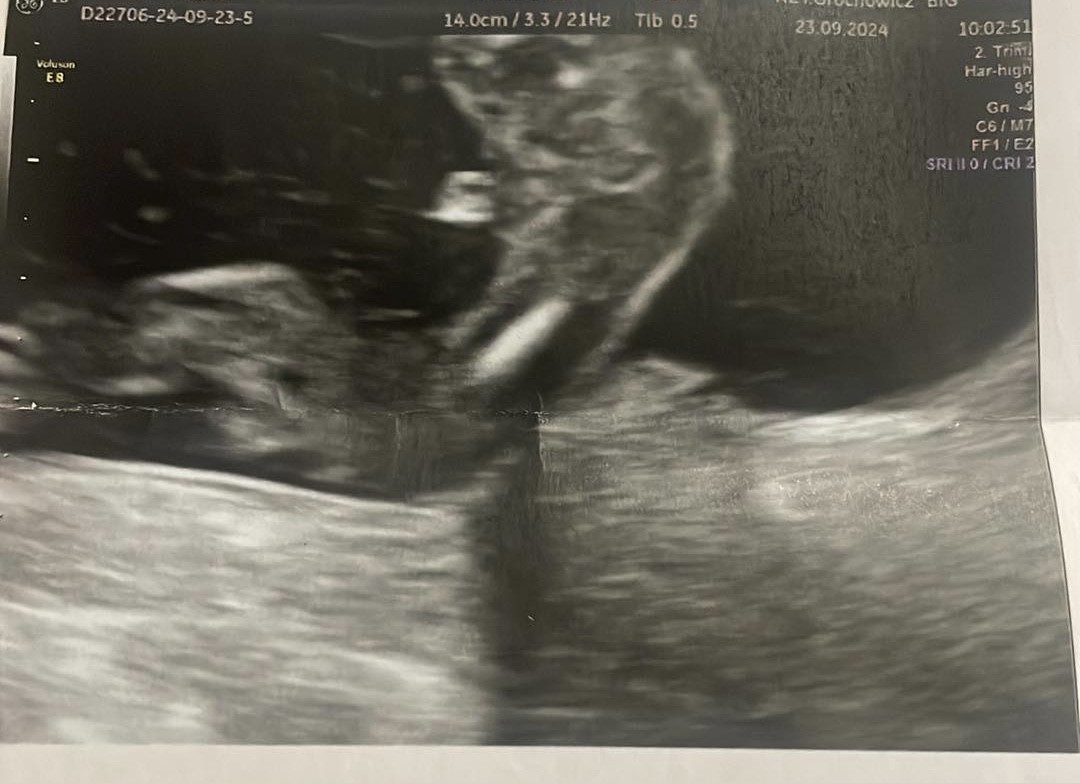

Zdjęcie usg 17tydzień

Dzień dobry mam zdjęcie z usg z 17tygodnia czy ktoś z was miał podobne zdjęcie lub się na tym zna i powie mi jaka jest płeć dziecka ? W 14 tyg doktor mówił że chłopiec teraz jednak się wacha a jak wy myślicie?